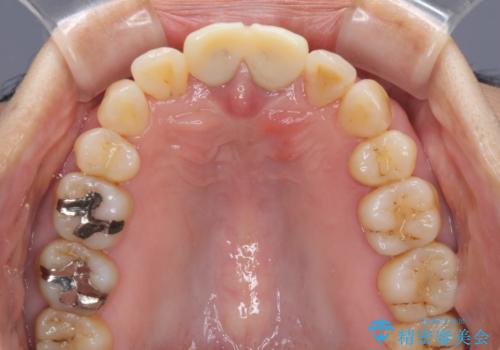

- 上の前歯の変色と、下の前歯のデコボコを気にして来院された患者様です。

前歯はオールセラミッククラウンに補綴することとしました。

補綴治療に先立ち、下顎前歯の部分矯正を行い、前歯の咬み合わせの安定性向上を図りました。

当初は上顎の補綴治療のみを希望されていましたが、奥歯にブリッジなど補綴物が多くあり、前歯も変色しているため、治療費が高額となってしまうことが懸念されました。

相談の上、最も気になっている前歯の部分矯正と補綴治療により口元の改善を図ることとしました。